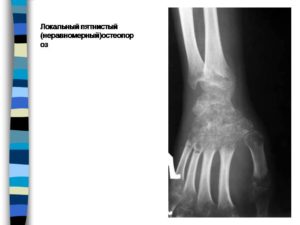

- Пятнистый, или очаговый, остеопороз захватывает отдельные, хаотично размещенные, участки кости. На рентгенограмме видны круглые или овальные очаги костной ткани с низкой плотностью. Пораженные сегменты могут иметь различную величину, форму и очертания. При пятнистом остеопорозе размер кости сохраняется, однако ее структура в некоторых местах становится пористой, что и приводит к излишней ломкости.

Основным способом диагностики является рентгенография поврежденной кости, которая пострадала от перелома. В ходе исследования можно обнаружить пятнистый остеопороз, для которого характерно образование участков с пониженной минеральной плотностью. Обычно такие участки имеют округлую форму и располагаются беспорядочно.

Признаки, на которые стоит обратить внимание: множество очагов повышенной прозрачности в дистальных отделах голени или фаланг, которые не имеют четких границ и проявляются на фоне неизмененной кости.

Пятнистая или очаговая разновидность локализуется в отдельных костных структурах. Очаговая форма определяется на рентгеновских снимках в виде участков с низкой плотностью костной ткани. Этим элементам присущи размытые очертания, разнообразной формы и величины.